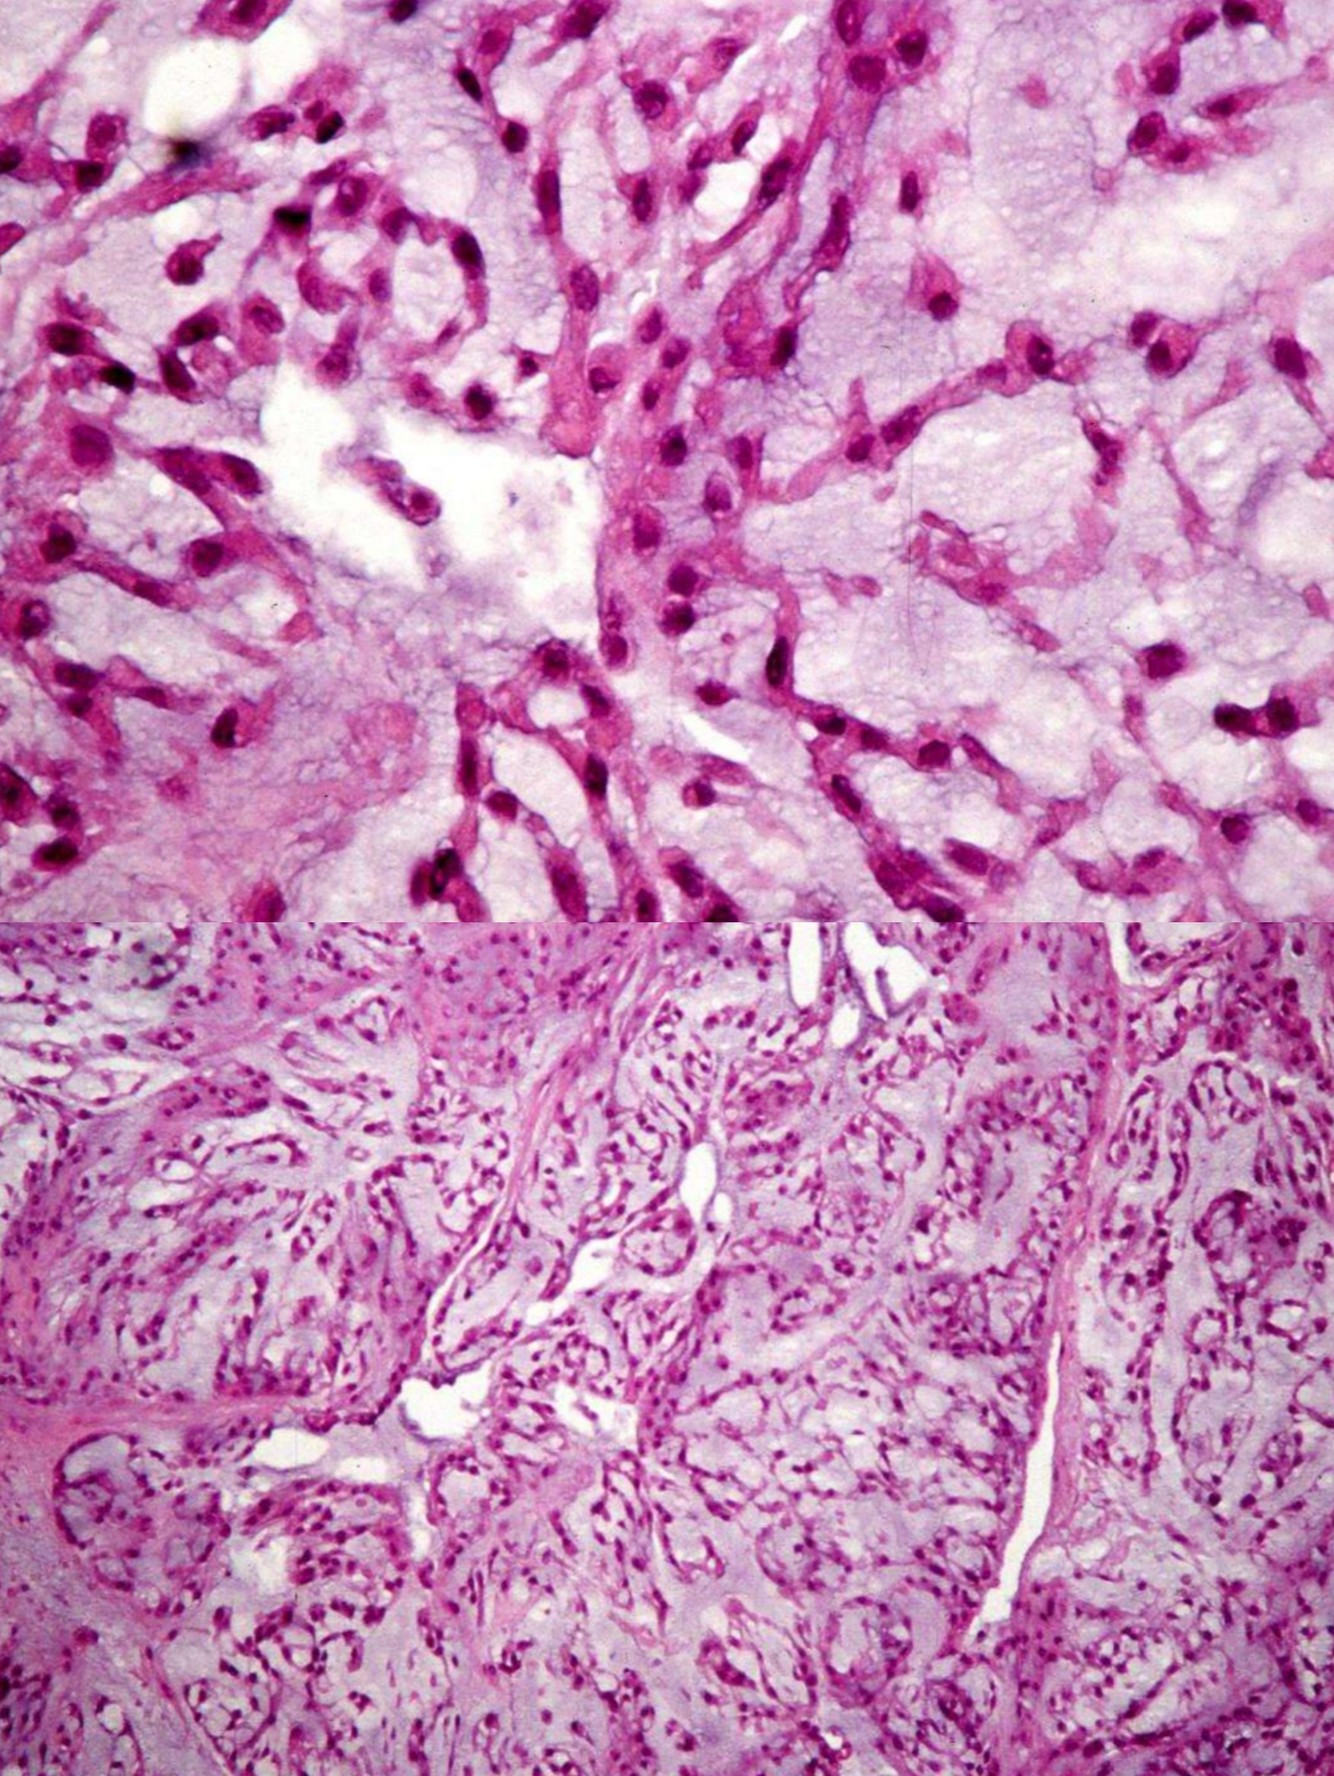

Myxofibrosarcoma

• Highly complex karyotypes, often 6p-, 9q+, 12q+

• A myxoid subtype of undifferentiated pleomorphic sarcoma

• elderly patients, predominately in extremities, 2/3 within dermis and subcutis, remainder in deep skeletal muscle or other deep tissues

• Retroperitoneal masses with similar histologic features are most likely dedifferentiated liposarcoma

• Gross:

• Superficial tumors are multiple myxoid nodules, deep tumors are a single mass with infiltrative margins

• High grade tumors often have tumor necrosis

• Histology:

• Multinodular tumor composed of pleomorphic spindle cells in myxoid background

• “Pseudolipoblasts” may be seen (tumor cells with cytoplasmic vacuoles filled with mucin/myxoid material)

• More solid areas are often seen similar to typical undifferentiated pleomorphic sarcoma

• Curvilinear vessels (thick walled with broad arc) with condensation of cells around vessels is characteristic, incomplete fibrous septa, myxoid stroma (at least 10% of tumor) and infiltrating immature dendritic cells (Am J Clin Pathol 2003;119:540)

• Has infiltrative periphery and often sends out long tentacles with frequent positive margins

• High grade tumors are more cellular with atypical mitotic figures, hemorrhage, necrosis and possibly bizarre multinucleated giant cells

• Rarely epithelioid

• Stains:

• No specific stains exists; +/- vimentin, acid mucins, CD34

• Negative: Fat stains, S100

Undifferentiated pleomorphic sarcoma

• Pleomorphic sarcoma composed of fibroblasts, myofibroblasts and histiocyte-like cells

• Diagnosis of exclusion; must sample generously and search for other components to rule out a dedifferentiated tumor or evidence of specific differentiation other than fibroblasts or myofibroblasts

• Usually older adults (age 50+ years) with slight male predominance; more common in lower extremities, rarely retroperitoneum, head and neck, breast

• Large and deep-seated with progressive enlargement

• Sarcomas adjacent to orthopedic implants or post-radiation are usually osteosarcoma or MFH

• Pleomorphic and bizarre tumor cells with foamy cytoplasm and marked atypia, in background of inflamed collagenous stroma

• Histologic types: storiform/pleomorphic, giant cell, inflammatory, myxoid

• Numerous mitotic figures, including atypical forms

• Rarely metaplastic (not neoplastic) bone or cartilage